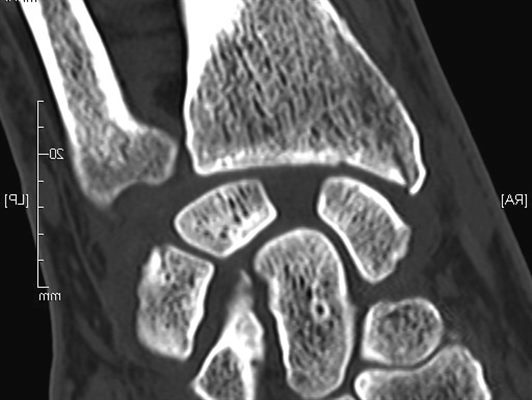

Les ruptures des ligaments du poignet concernent principalement le ligament scapho-lunaire situé au centredu poignet et le ligament triangulaire (TFCC) situé au bord interne du poignet. Leurs lésions sont post traumatique après une chute sur le poignet en extension ou par torsion. Le diagnostic est faitdevant des douleurs spontanées localisées au bord ulnaire (TFCC) ou centrale au milieu du poignet (ligament scapho-lunaire), et lors des mobilisations du poignet. Des phénomènes de ressauts sontparfois ressentis.